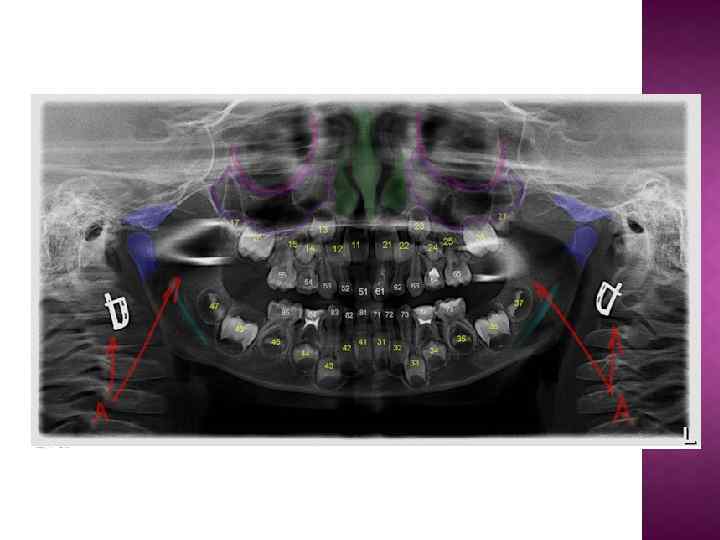

Большинство стоматологических материалов изготавливаются рентгеноконтрастными. Делается это для того, чтобы можно было контролировать объем и расположение этого материала на рентгеновских снимках. Например, пломбировочные материалы для корневых каналов на снимке обозначены буквой А. Ортопантомография дает хорошее представление о расположении зубов мудрости (на снимке буква С). Даже прицельные снимки не дают полной картины о строении и локализации восьмерок. Поэтому без проведения ОПТГ я крайне не рекомендую браться за удаление или лечение "мудрых" зубов.

Проникновение корней зубов в верхнечелюстную пазуху (буква B на снимке). На самом деле, корни зубов ооочень редко проникают в верхнечелюстной синус. Чаще всего они огибают его по краям таким образом, что дно пазухи находится между корней зубов.